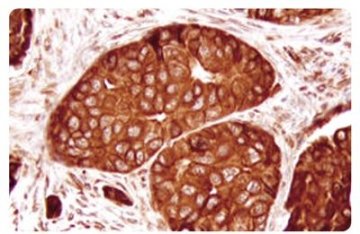

• 病理金标准如何不褪色

病理金标准如何不褪色

上海市临床病理质量控制中心主任 杜 祥病理精准诊断指导临床合理治疗一名15岁的中学生因小腿有包块、剧痛到当地医院就诊,病理诊断为骨